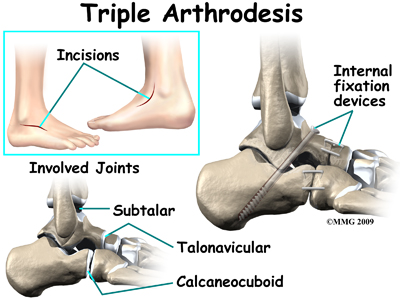

The most common surgical procedures used with this condition include arthrodesis (fusion), osteotomy (cutting out a wedge-shaped piece of bone), and lateral column lengthening. Lateral column lengthening involves the use of a bone graft at the calcaneocuboid joint, which helps restore the medial longitudinal arch (arch along the inside of the foot).

Significant improvement in your foot after surgery occurs gradually over a four-to-six month period of time. During that time, your physical therapist will progress your exercise program, but your appointments at Ari Levine PT, PC will decrease in frequency. For those patients who have had a fusion, there will be some stiffness and loss of motion in the foot and/or ankle, so this should be expected. The amount and location of the stiffness depends on which bones were fused together.